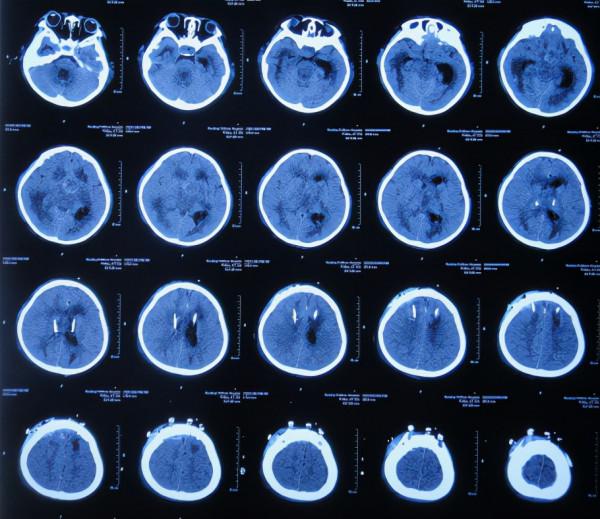

在第4家醫院治療26天期間內,三次複查頭部CT(圖-29、圖-30、圖-31)均示腦積水,右側顳角明顯擴。

圖-29:2020年4月23日頭部CT

圖-30:2020年5月7日頭部CT

圖-31:2020年5月18日頭部CT

看著患兒病情無好轉,家屬心急如焚,在網上找到李小勇腦脊液科經確認後於2020年5月19日(在第4家醫院治療26天)從安徽省蕪湖市轉入北京北亞骨科醫院的李小勇腦脊液科。

二、李小勇腦脊液科治療過程和結果

2020年5月19日(在半年時間內先後經4家醫院治療,即顱內腫瘤切除術後145天又即顱底腫瘤切除術後49天,仍反覆腦積水)轉入李小勇腦脊液科。入院時:體溫發熱38.5°C,意識模糊,左側肢體偏癱,體型偏瘦(圖-32)。

入院當天頭部CT示右側顳角擴張,腦室內有3根管(圖-33)。

圖-33:2020年5月19日頭部CT

入院治療7天即2020年5月26日,複查頭部CT示右側顳角縮小(圖-36)。

圖-36:2020年5月26日頭部CT

入院治療15天即2020年6月3日,查頭部CT示兩側腦室均縮小(圖-38)。

圖-38:2020年6月3日頭部CT

入院治療69天即2020年7月27日,頭部CT示腦室未見異常(圖-44)。

圖-44:2020年7月27日頭部CT

入院治療74天即2020年8月1日,進行了腦室腹腔分流術(圖-45)。

圖-45:2020年8月1日頭部CT

入院治療104天即2020年8月31日出院。出院時頭部CT示未見異常(圖-46);由入院時的意識模糊,左側肢體偏癱,體型偏瘦好轉為:意識清楚,言語交流變正常,左側肢能遵囑活動但力量稍差,體型變微胖(圖-47);腦瘤術後遺留部分記憶失去。

圖-46:2020年8月31日出院時

圖-47:2020年8月31日頭部CT